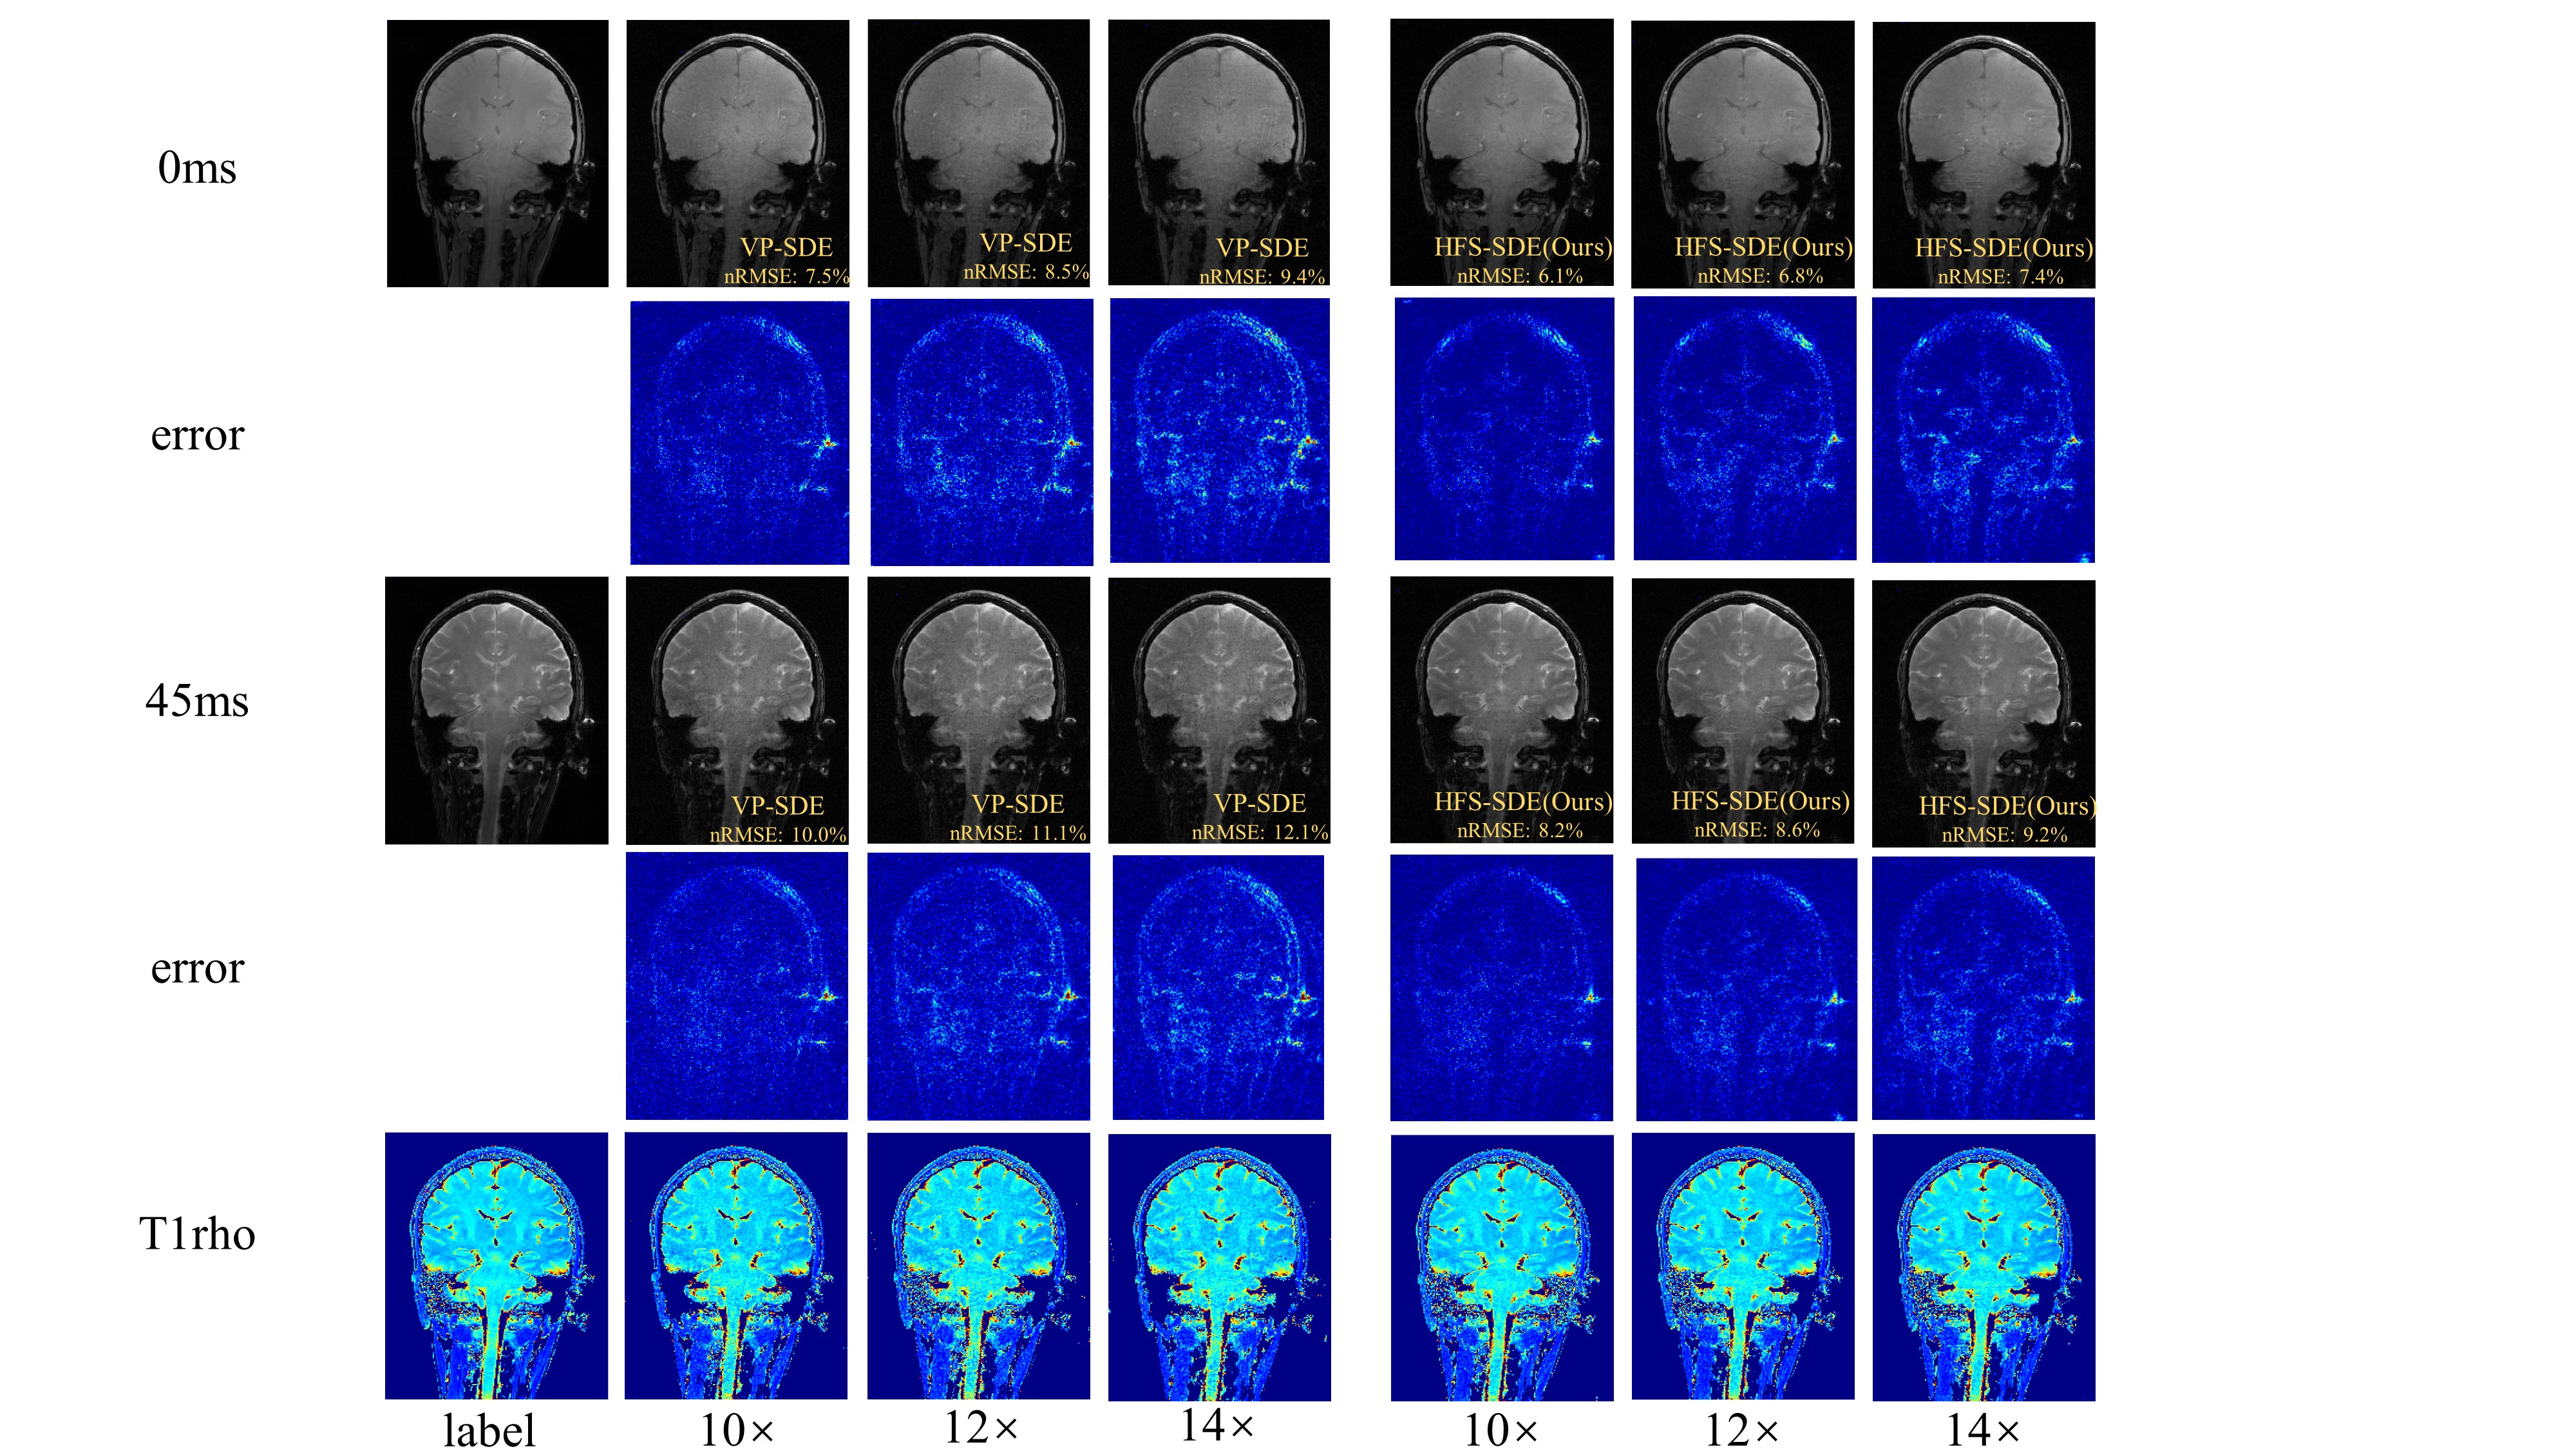

Figure 2 shows the reconstructed T1ρ-weighted images and the corresponding maps of the coronal view using HFS-SDE at acceleration factors of 10, 12, and 14. The reconstruction results of VP-SDE are also shown for comparison. We calculated the normalized root mean squared error (nRMSE) of each image. The nRMSE is shown in the lower right corner of each image. As can be seen from the results, the reconstructed images using HFS-SDE show little artifacts and have lower nRMSE compared with those using VP-SDE. Figure 3 shows the reconstructed results in the sagittal view. A similar conclusion can be drawn from Figure 3 as from figure 2.

Figure 2: Reconstructed T1ρ-weighted images and the corresponding maps of the coronal view using VP-SDE and HFS-SDE at acceleration factors of 10, 12, and 14.

Figure 3: Reconstructed T1ρ-weighted images and the corresponding maps of the coronal view using VP-SDE and HFS-SDE at acceleration factors of 10, 12, and 14.